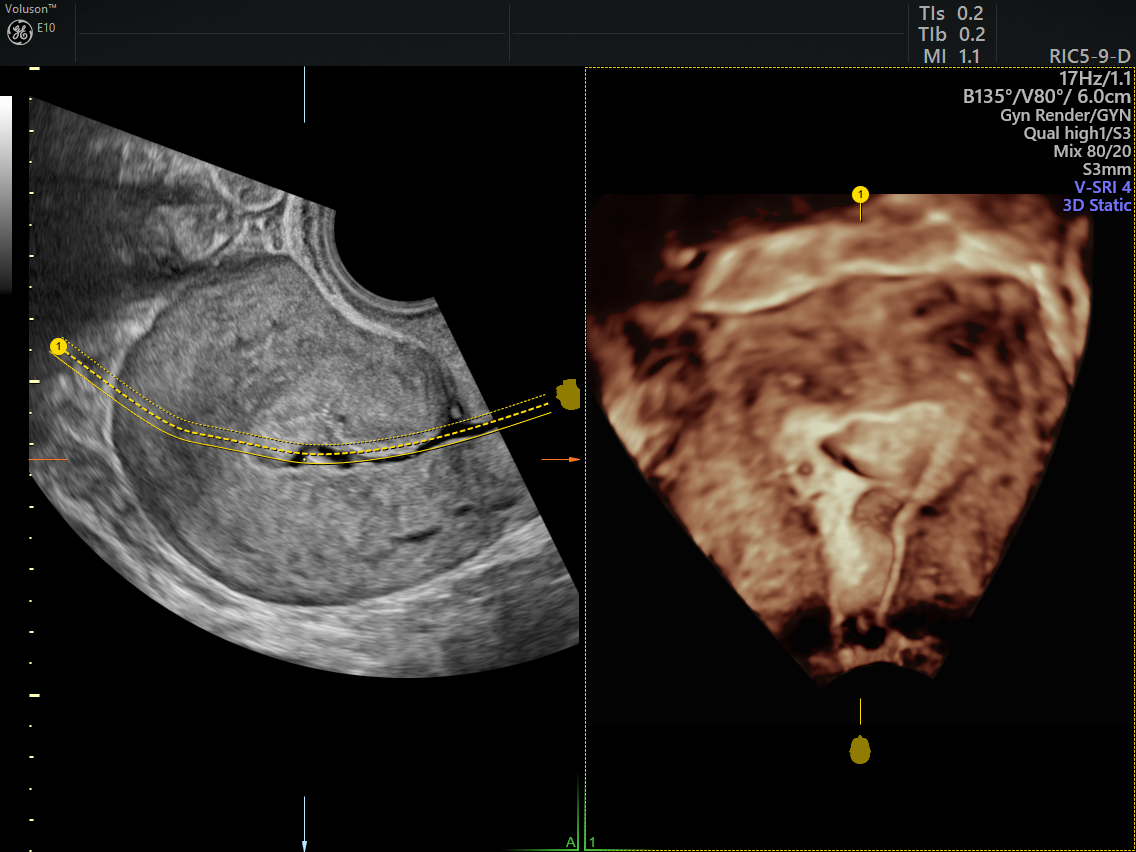

Fan Shaped Adenomyosis . Musa features typical of a uterus with. Adenomyosis is a clinical condition where endometrial glands are found in the myometrium of the uterus. Adenomyosis has been described as both diffuse and focal, depending on its distribution within the myometrium. One in three patients with. We reviewed the literature to summarize the available classification systems for adenomyosis and highlight the different imaging approaches and histologic criteria used in.

Adenomyosis Ultrasound Empowered Women's Health Fan Shaped Adenomyosis Adenomyosis has been described as both diffuse and focal, depending on its distribution within the myometrium. Musa features typical of a uterus with. Adenomyosis is a clinical condition where endometrial glands are found in the myometrium of the uterus. We reviewed the literature to summarize the available classification systems for adenomyosis and highlight the different imaging approaches and histologic criteria. Fan Shaped Adenomyosis.

Ultrasound imaging Adenomyosis uterus Fan Shaped Adenomyosis Musa features typical of a uterus with. Adenomyosis is a clinical condition where endometrial glands are found in the myometrium of the uterus. One in three patients with. We reviewed the literature to summarize the available classification systems for adenomyosis and highlight the different imaging approaches and histologic criteria used in. Adenomyosis has been described as both diffuse and focal,. Fan Shaped Adenomyosis.